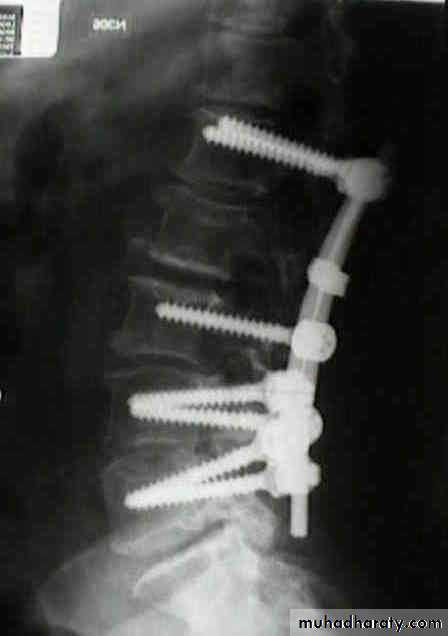

BURST FRACTURE OF A VERTEBRAL BODY

frcature spine and peripheral nerve

the compression force thus acts vertically in the line of the vertebral bodies.

The intervertebral disc is forced

In the affected vertebral body, causing a comminuted bursting fracture in which fragments are driven outwards in all directions.

Treatment

If there is no neurological impairment, it is permissible to employ

Conservative treatment as for wedge compression fracture, but a rather longer period of recumbency is advisable.

Some surgeon advise surgical fixations.